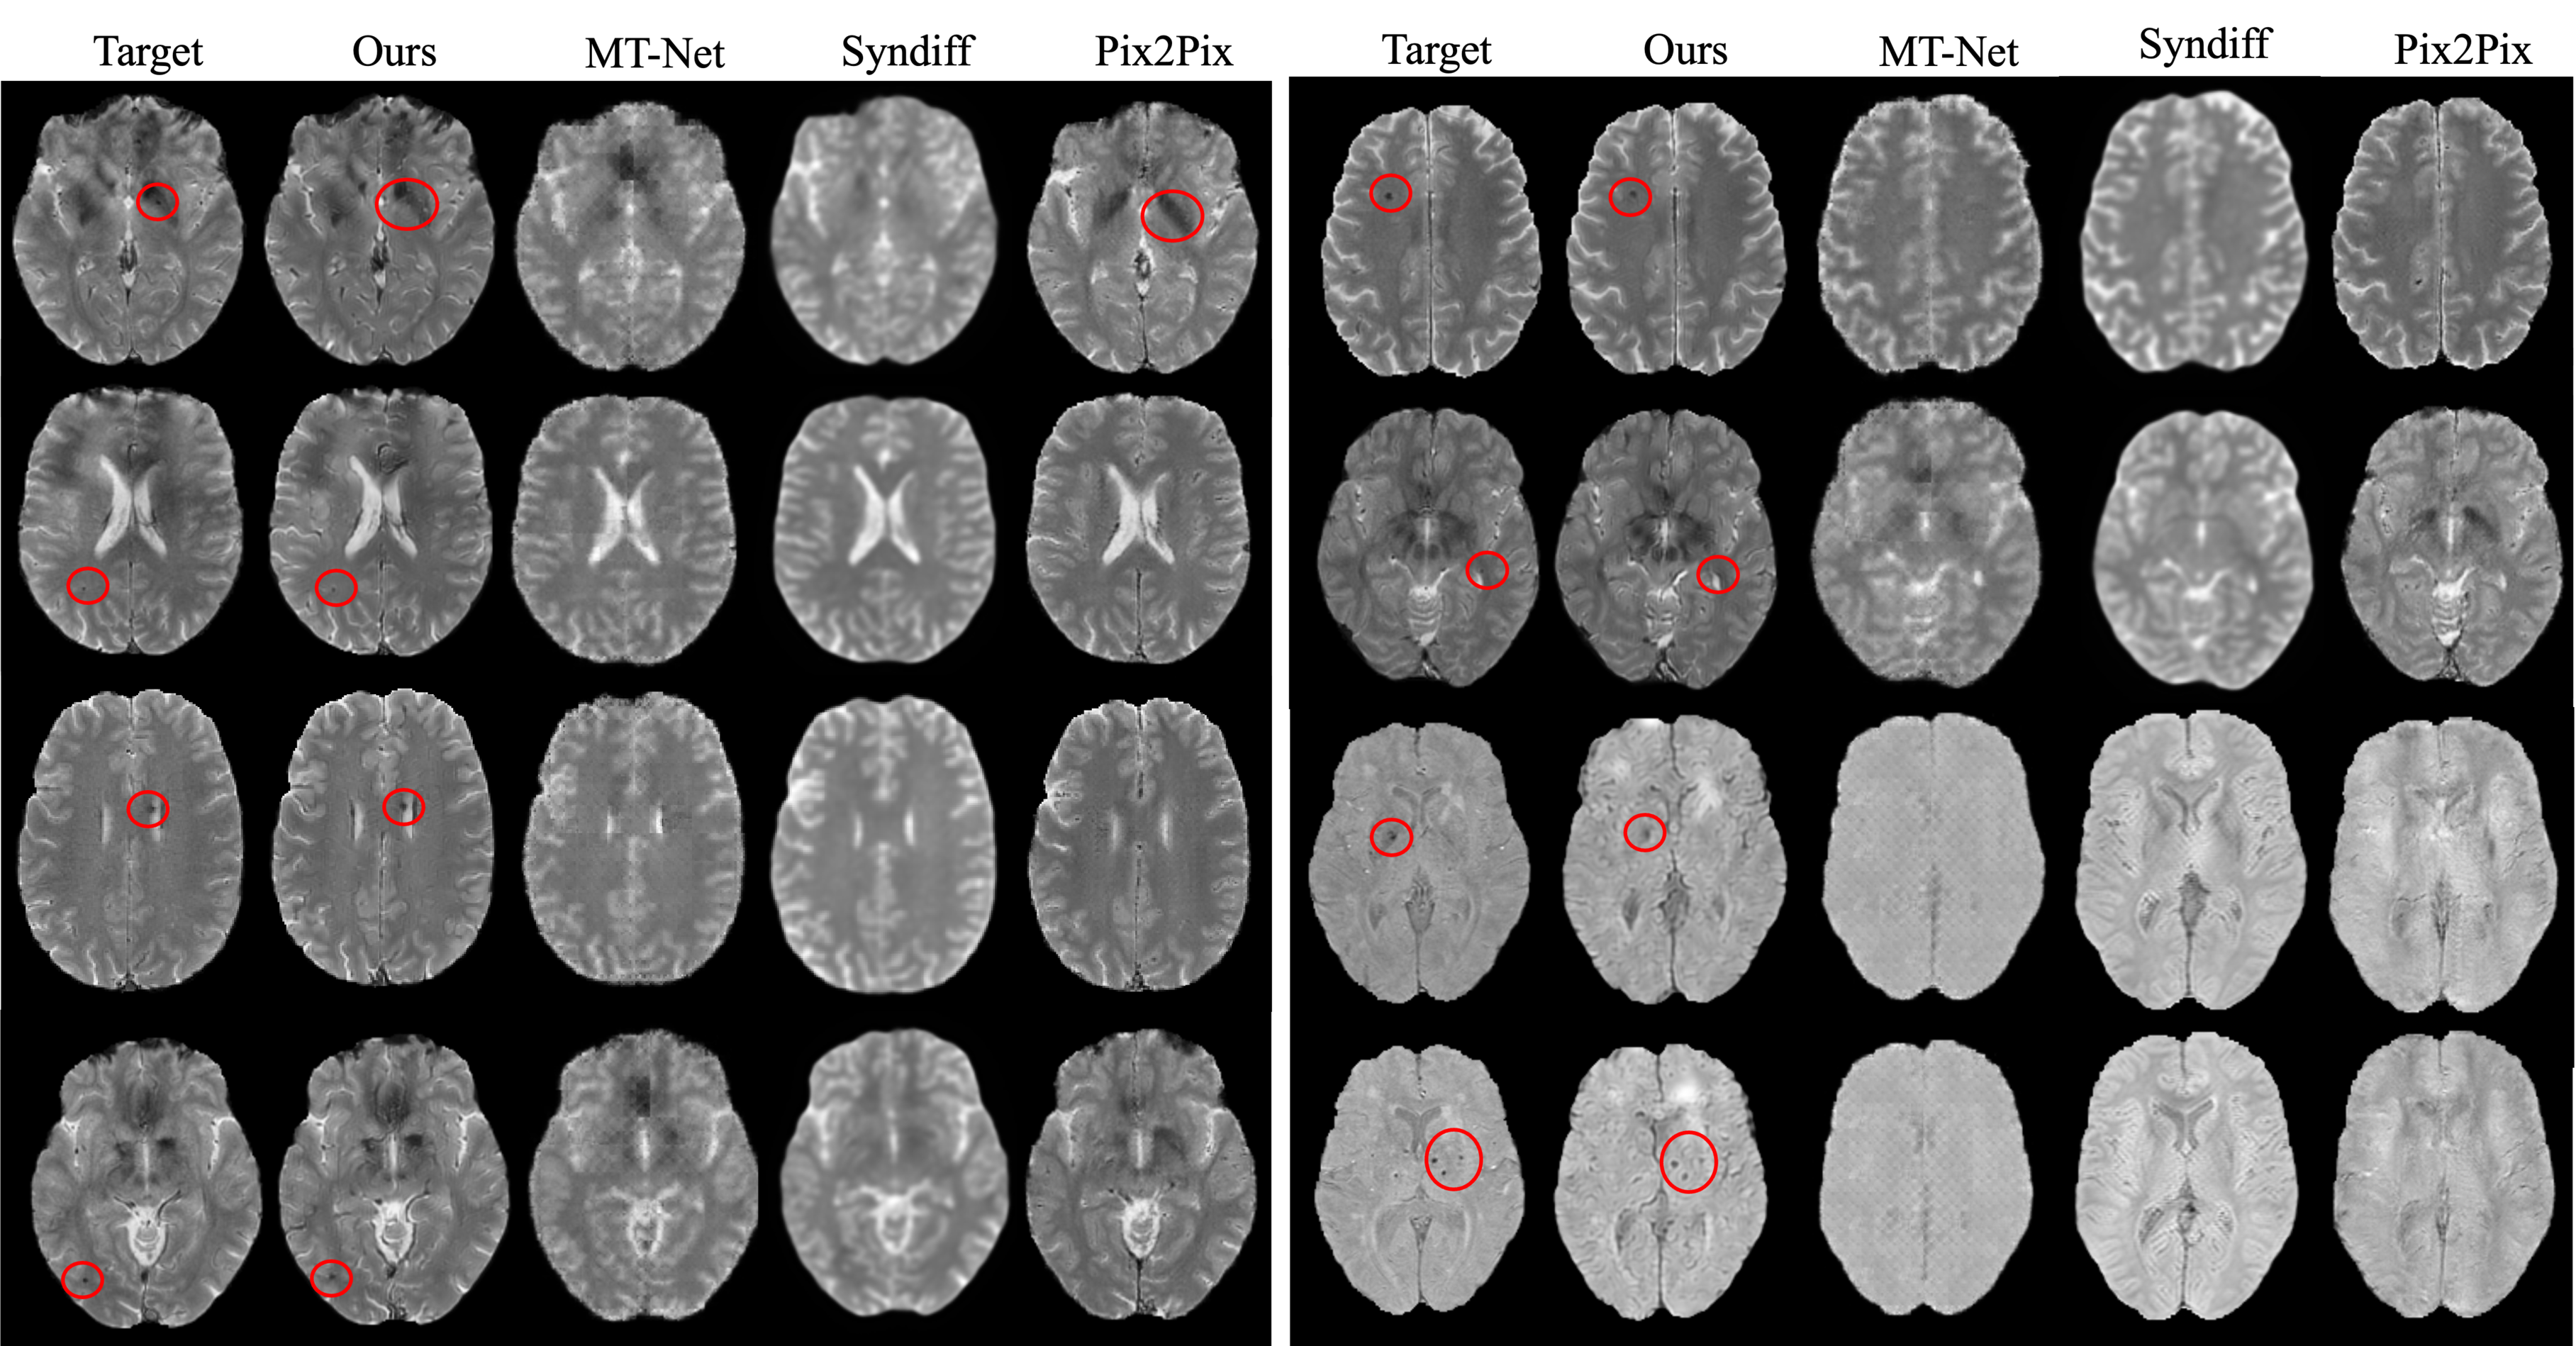

4.1.5 VALDO

T2 star(T2*) synthesis from T1w was demonstrated for two applications: (1) T2* using about 400/180 axial slices from 19/8 subjects (training/test), and (2) T2* GRE synthesis using 70 slices from 24/10 (training/test) subjects. All images were spatially co-registered.

5.1 Brain MR Image synthesis result

All experiments used T1w as the source modality, which serves as an optimal source sequence for synthesis due to its rapid acquisition time, clinical efficacy, and superior anatomical delineation [41]. The numbers in parentheses indicate the number of subjects used for training. For MT-Net, the format shows (pre-training subjects/fine-tuning subjects).

Our FGSB framework demonstrates exceptional data efficiency, achieving competitive or superior performance with dramatically fewer training subjects compared to existing methods(2, 3, 4, 5). Remarkably, FGSB trained on only 2-3 subjects consistently outperforms baseline methods trained on 10-25 subjects, while matching or exceeding state-of-the-art performance when using comparable training data. Our framework excels in preserving clinically essential structures, particularly lesions and white matter hyperintensities (WMHs), which are often lost or distorted by competing methods.